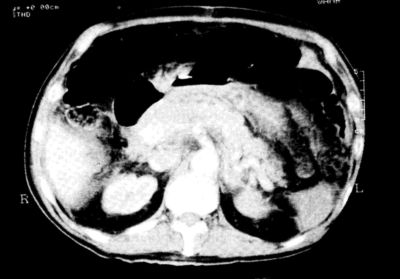

Pozitívum volt azonban az epigastrialis érzékenység (izomvédekezés nélkül) és a bélhangok hiánya. A hemicolectomia után, a távozás napján a beteg Hgb értéke 10,9 g/l volt, az újrafelvételkor 5,8 g/L A klinikai tünetek és a Hgb- érték ismeretében intenzív shock-ellenes folyadékterápiát és transfusiót kezdtünk. Tekintettel arra, hogy a beteg sem hae- matemesisről, sem melaenáról, illetve rectalis vérzésről nem számolt be, és a fentiekre utaló tüneteket a vizsgálat során sem találtunk, intraabdominalis vérzés gyanújával sürgős hasi UH-vizsgálatot kértünk, mely a has jobb felében, sub- hepaticusan, illetve a colon ascendens mentén több száz ml- nyi szabad hasűri folyadékot igazolt (Dr. Gould). Az intraabdominalis vérzés diagnózisával sürgős laparotomiához készültünk. Az előkészítés alatt az intenzív folyadékterápia és a transfusiók hatására a beteg haemodinamikailag stabilizálódott, s miután az elózó műtét során semmiféle potenciális vérzésforrást nem sikerült találni, a laparotomia előtt, a folyadékterápiát folytatva, sürgős CT-vizsgálatot végeztünk (dr. Gould). Ez egyértelműen kimutatta a vérzésforrást: meszes, aneurysmaticus truncus coeliacus, körülötte álaneurysma, hatalmas thrombussal. (2. ábra.)

2. ábra.

A felvétel középpontjában az aorta, az aortából kiinduló meszes, aneurysmaticus truncus coeliacus, és körötte a hatalmas álaneurysma.

A következő felvételen (3. ábra) még egyértelműbben látszik a képletek egymáshoz való viszonya, míg a 4. ábrán a truncus coeliacus már nem látható, csak az aorta keresztmetszete, és az átmérőjében ennél kb. háromszor nagyobb, hatalmas álaneurysma.